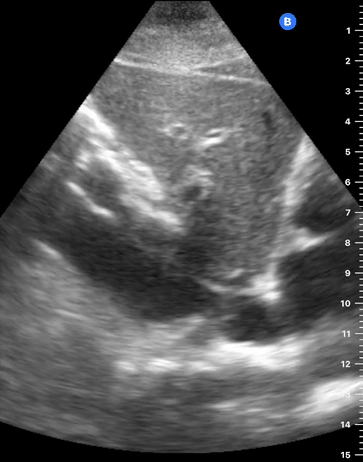

The IVC diameter changes depending on intravascular volume status, and normally, the IVC collapses during spontaneous inspiration. Therefore, the IVC diameter represents a non-invasive method for estimating central venous pressure (CVP). The evidence suggests that in spontaneously breathing patients, there is a good correlation between the sonographic estimation of CVP and values measured with invasive methods (2). IVC filling and CVP, however, allow only a rough correlation with volume status, and the sonographic estimation of preload should at least include the assessment of the LV and the Lung. Thus, it is better to think of IVC filling as an indicator of fluid tolerance, instead of a determinant of fluid responsiveness (6).

IVC exploration is best from the subxiphoid approach with longitudinal and transverse images. The IVC should be assessed in terms of overall size and collapsibility. The diameter is typically measured at its largest (end of expiration) at 1-2 cm distal to where the hepatic veins join the vena cava. An IVC diameter of ≥ 2 cm, especially with minimal or no collapsibility, is considered plethoric and correlates with increased RA pressure. An IVC of < 1 cm, particularly with complete collapse, is considered flat and indicates low preload and potential fluid responsiveness. An IVC diameter between 1 and 2 cm is typically normal.

PITFALLS

In a long-axis view, beware of not sliding off the centre of the vessel, as this will underestimate the size of the IVC and overestimate its collapse. Obtaining long and short axis views may help avoid this pitfall. Another mistake is confusing the descending aorta for the IVC, particularly when scanning in long-axis. Although the IVC may appear to pulsate, the aorta has a thicker wall, and its position is to the patient’s left. Following the IVC upwards will reveal the hepatic veins junction and the entrance to the RA, while the aorta will travel behind the heart. The IVC moves both anterolaterally and craniocaudally with inspiration, and this should be considered during visualization or measuring. For this very reason, measuring in M-mode is not recommended as it would not be accurate.

SHOCK

In a shocked patient, a flat or highly collapsible IVC correlates well with low preload estates (hypovolaemia, haemorrhage, sepsis). Yet by itself, a small IVC is not enough to define low preload and could also represent a normal finding.

Conversely, a distended, not collapsing IVC suggests distal obstruction in a shocked patient. Potential causes include LV failure, massive PE, tension pneumothorax and cardiac tamponade. Nonetheless, there are other causes of elevated cava / RA pressure, such as chronic pulmonary hypertension.